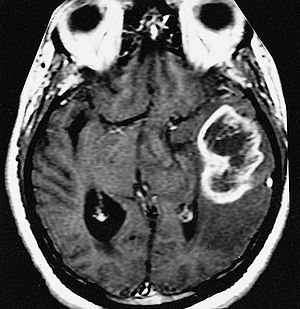

AFIP-00405558-Glioblastoma-Radiology.jpg

An example of a ring-enhancement around a lesion in gliobastoma. In tumefactive multiple sclerosis, the ring-enhancement is open, not forming a complete ring.

Diagnosis of tumefactive MS is commonly carried out using magnetic resonance imaging (MRI) and proton MR spectroscopy (H-MRS). Diagnosis is difficult as tumefactive MS may mimic the clinical and MRI characteristics of a glioma or a cerebral abscess. However, as compared to tumors and abscesses, tumefactive lesions have an open-ring enhancement as opposed to a complete ring enhancement.[1] Even with this information, multiple imaging technologies have to be used together with biochemical tests for accurate diagnosis of tumefactive MS.[36]